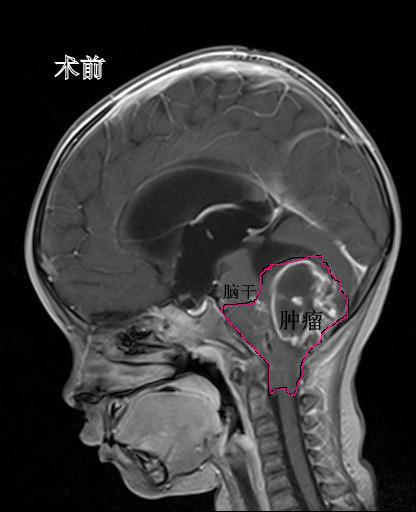

心急如焚的家长急忙将孩子送到温医大育英儿童医院儿童内科就诊。接诊的儿科医生检查发现,孩子的呼吸道疾病表现并不是很严重,反而是全身不适症状明显,精神状态不佳,考虑可能是头颅占位性病变,于是给俊俊做了脑部CT和核磁共振。检查的结果着实让人大吃一惊,年仅2岁多的俊俊后脑竟长了个7cm*5cm*6.5cm,足足有鹅蛋大小的肿瘤。这一结果吓坏了俊俊一家人。孩子从小生长发育都很正常,以前也没有出现过长期头痛的症状,知道孩子颅内长了肿瘤,家里人很难接受。当天,俊俊就被迅速转送到了儿童神经外科。

术前MR检查发现后颅窝巨大占位,脑干被肿瘤包绕

“图像报告显示这颗巨大的肿瘤紧紧包住了四分之三的脑干和好几条神经血管,手术风险极大。我们都知道脑干维持个体生命,包括心跳、呼吸、消化、体温、睡眠等重要生理功能,是人体的生命中枢,稍有不慎就可能造成无法挽回的损失。但这还不是当务之急,”林坚主任说,“迫在眉睫的是肿瘤堵塞了脑脊液的循环通路,造成了大量的脑积水,如不及时处置,不但肿瘤切除手术没法做,孩子随时都有呼吸骤停甚至死亡的可能,必须马上实施脑室外引流术。”